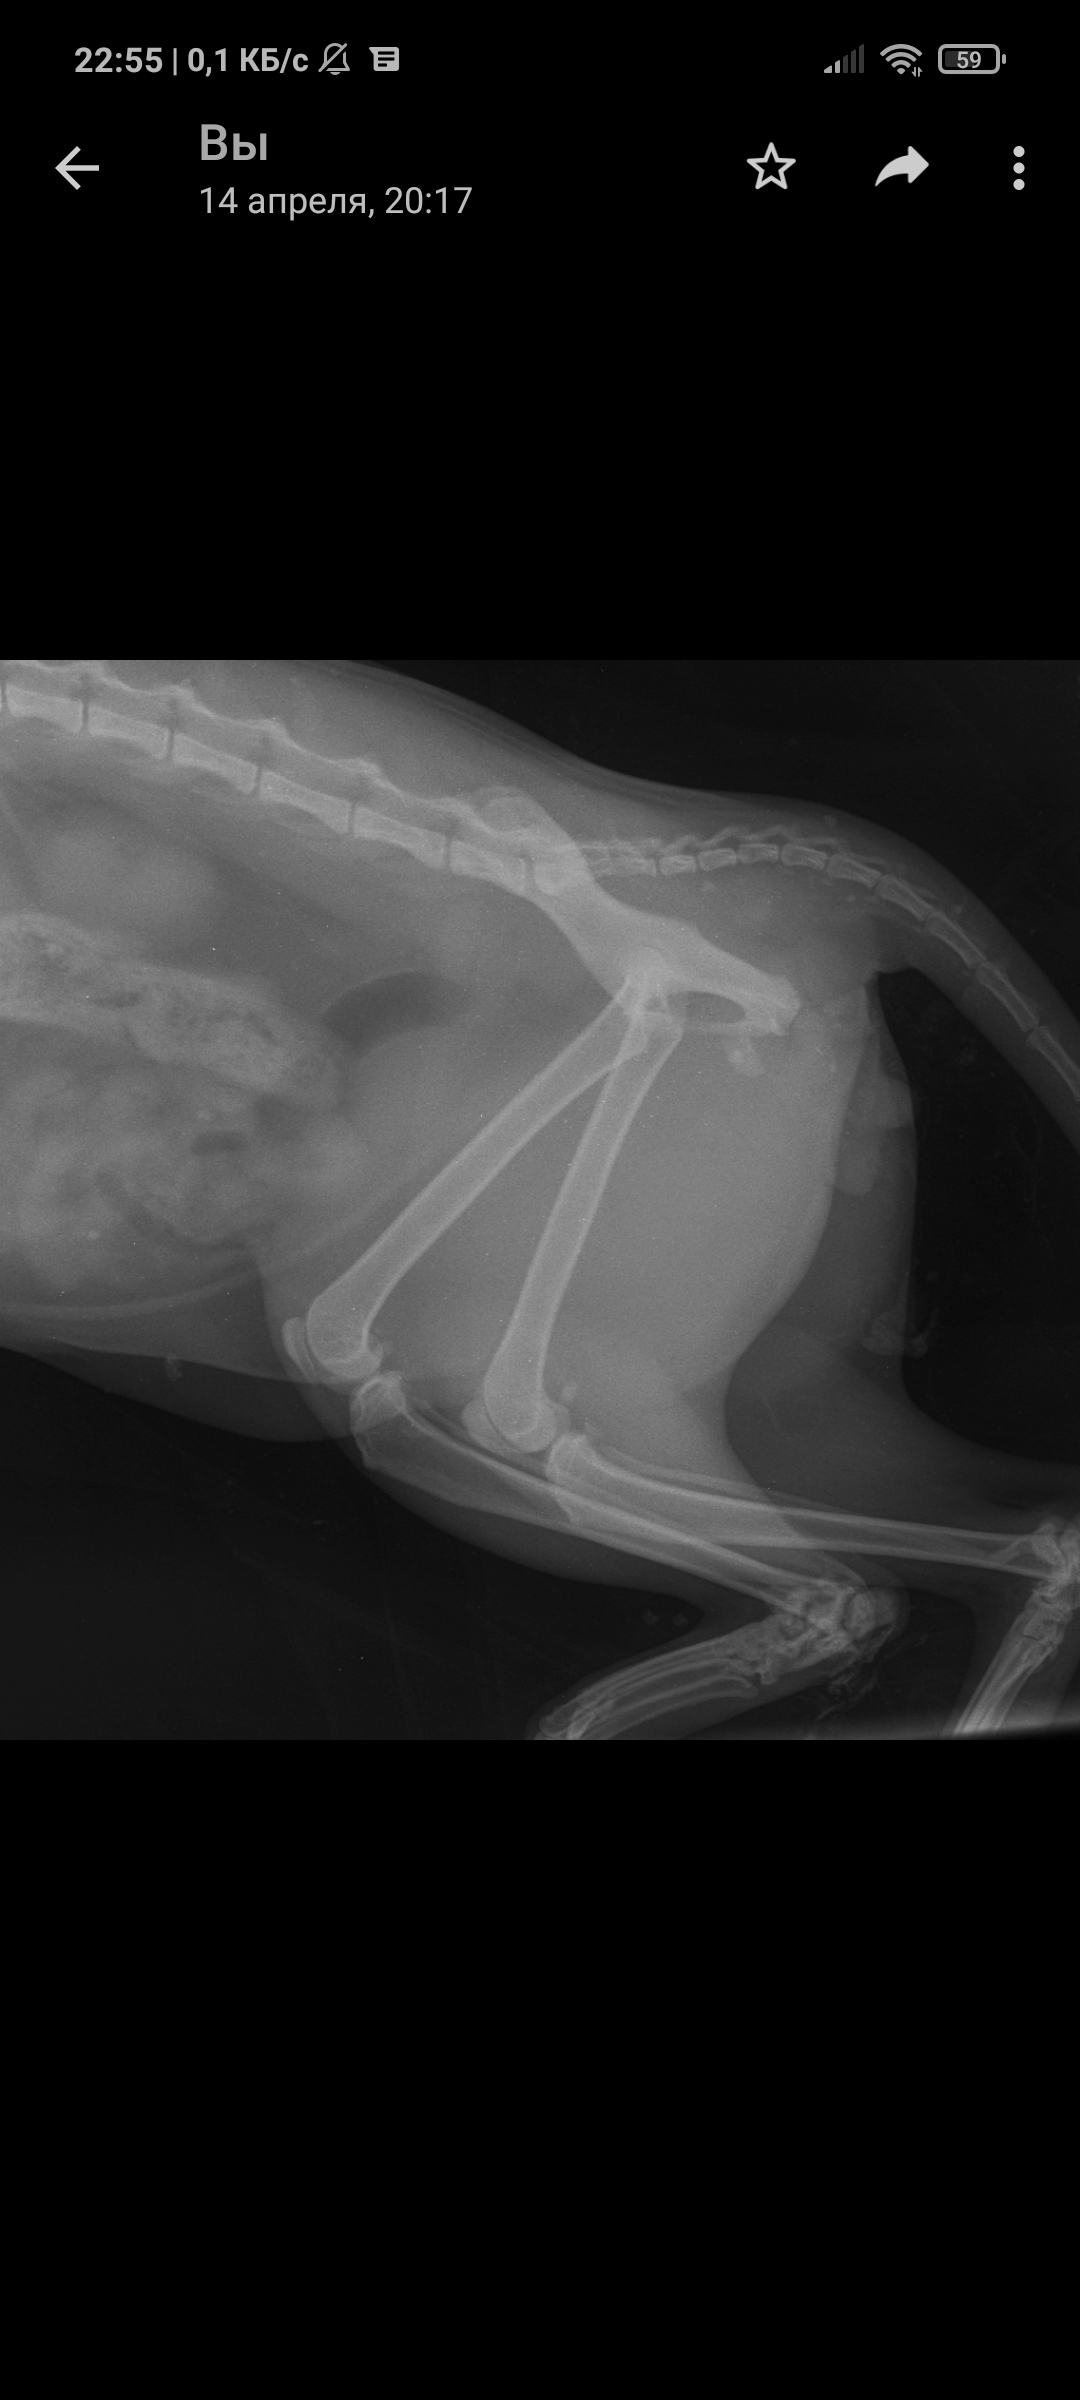

Так уж получилось что я ветеринарный врач, работаю в интенсивной терапии - принимаю и лечу самых тяжелых животных. На днях ближе к ночи прибегает женщина с котом, который шлёпнулся перед ней на улице. При осмотре выясняется что кот в шоке - лежит на боку, без давления, температуры, у него сломаны передние лапы, лицо, пневмоторакс и немного жидкости в брюшной полости (вероятно кровь). Женщина оставляет двадцатку на первые сутки и идет искать хозяина, кот помещается в стационар для стабилизации состояния. Всю ночь я ебусь с этим котом, вывожу его из шока, спускаю ему пневмоторакс, грею, обезболы льются рекой, к утру кот похож на кота, а не на покойника - начал садиться, ползать, полизал еду.

В общем, четвертый день от падения, полет нормальный, кот начал есть сам, а я иду на смену, ждите новостей, думаю скоро будет пост про то, как мы оперируем животных, в частности собираем ходули герою этой истории 😁